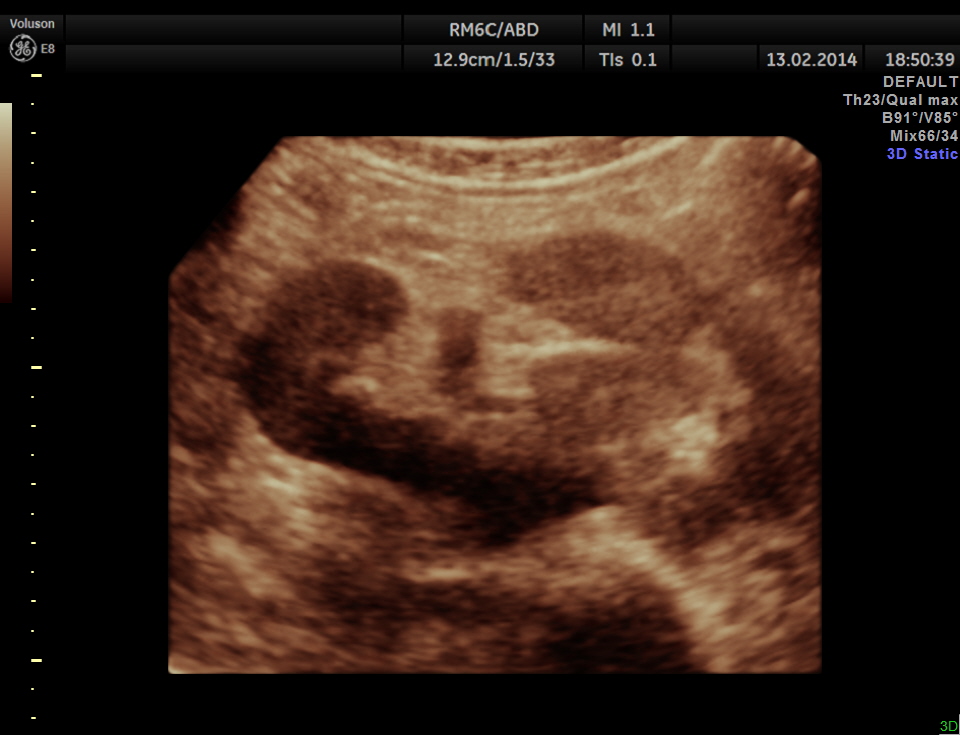

The following are the pictures of the kidney , which show the congenital horse shoe kidneys , placed ectopically in the pelvis. He had no urinary symptoms or low back ache at any time .

The right and left portions of the horse shoe are shown separately below

some of the reconstructed images are given below.